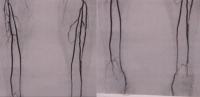

Filmbeispiel: AVK Stadium IIb rechtes Bein mit subtotaler Stenose der Arteria iliaca externa, Arteria femoralis communis-Verschluss, Profunda-Abgangsverschluss, langstreckiger Verschluss der Arteria femoralis superficialis, Verschluss der Arteria tibialis anterior beidseits (rechts proximal, links peripher) -> TASC D